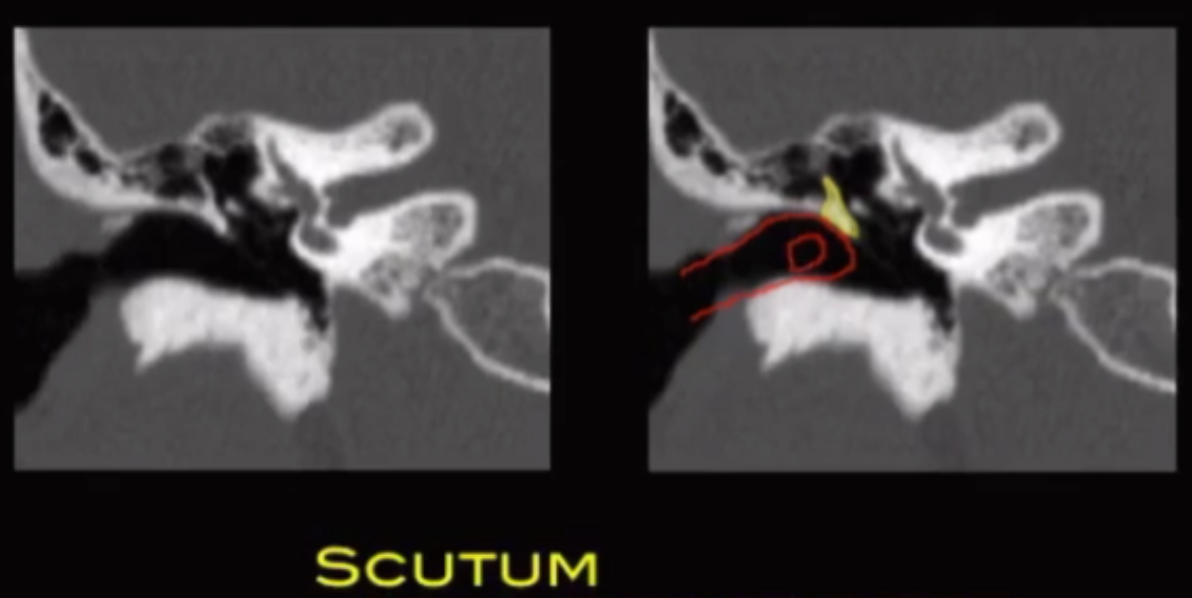

Cholesteatoma

• Scutum is where erosion will occur first

• Scutum = shield = blocks shit that enters your ear from hitting the ossicles

• Lateral semi-circular canal (red semi circle in image below) will be the first affected by cholesteatoma